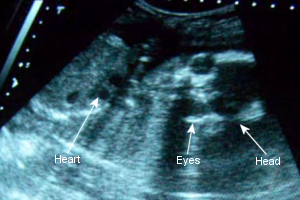

Sono Pic:

21 weeks

October 22nd: I gained 3 pounds in 3 weeks, which is fine, but I now weigh 137 lbs., which is 2 pounds more than I weighed when I gave birth to Alaethia! I was hoping we could see the baby’s little privates, but she had her legs crossed and wouldn’t let us see. Still, the doctor assured me she’s probably still a girl. I hope so! We still don’t have a name for her. I spent so much time reading that darn baby book and nothing stands out!